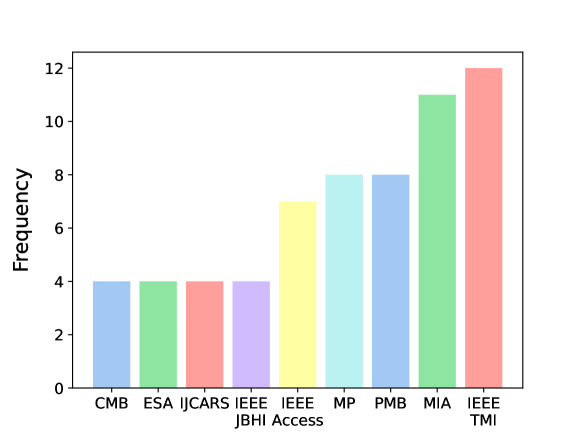

The database search retrieved 2,851 results. After title and abstract screening, the full texts of 206 reported studies were analyzed, but only 140 were found eligible for inclusion. Twenty studies using imaging acquisition other than CT (magnetic resonance imaging (MRI), positron emission tomography (PET), and ultrasound) were excluded. The list of excluded articles and the reasons for exclusion are reported in Section 2.5. Ten additional studies were retrieved after a manual check of the references. A total of 130 studies were included for full-text analysis (Fig. 2). By considering the involved countries (Fig. 3, left panel), China led the ranking with a share of 54.4%, followed by the United States (17.1%), the United Kingdom (5.3%), Canada (3.5%), and Japan (3.5%). In the majority of studies, 3D neural networks (Fig. 3, central panel) were used (51.4%), followed by 2D models (42.7%), and 2.5D (5.8%). By considering the learning type, the vast majority concern studies on supervised learning (83.8%), followed by semi-supervised learning (9.5%), and unsupervised learning (4.4%). Other types of learning (reinforcement, weakly, and continual) are reported in 2.2% of the studies (Fig. 3, right panel). Overall, there is a positive trend in the number of published articles in peer-reviewed journals, included in the present review, even though the data for the year 2023 are available until October 31st (Fig. 4). Notably, there has been a surge in the number of studies on DL for the segmentation of pancreas tumors in 2023. The 130 reviewed studies were published in high-quality peer-reviewed journals with a mean 2023 impact factor of 5.39 (latest available data according to the Web of Science). As can be seen from Fig. 5 the studies were most frequently published in prominent journals in the medical imaging domain, like Medical Imaging Analysis and IEEE Transactions on Medical Imaging, with 11 and 12 publications, respectively. Of note, there are other studies published in leading journals like IEEE Transactions on Pattern Analysis and Machine Intelligence, IEEE Transactions on Image Processing, and Nature Methods.